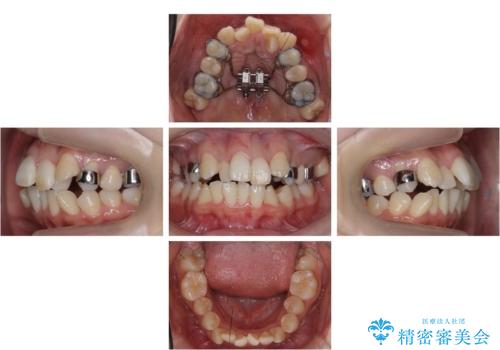

難症例 奥歯がかみ合っていない 歯並び矯正で別人に

前歯は重度のがたつき、また奥歯はすれ違っていました。

治療は3年以上かかりそうと説明しましたが、2年台で終わらせることができました。

上下左右4本抜歯の可能性を説明していましたが、実際は上顎2本の小臼歯抜歯で済みました。

矯正用インプラントを使用して治療しています。

上下の顎の幅もあっておらず、成人でしたが手術なしで上あごを骨から広げる処置(急速拡大装置)を行いました。